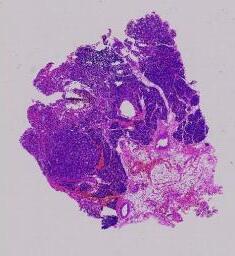

临床资料: 患者:女,年龄:65岁,发现肾上腺肿物2月,入院CT示:右侧肾上腺区占位性病变,大小4.7×4.3cm,实验室检查:血儿茶酚胺明显升高,临床诊断:嗜铬细胞瘤待查

大体所见: 灰白色不整形组织一块,大小6.0cm×5.0cm×3.5cm,切开切面灰黄色,实性,质地中等,局部区域见出血、坏死。